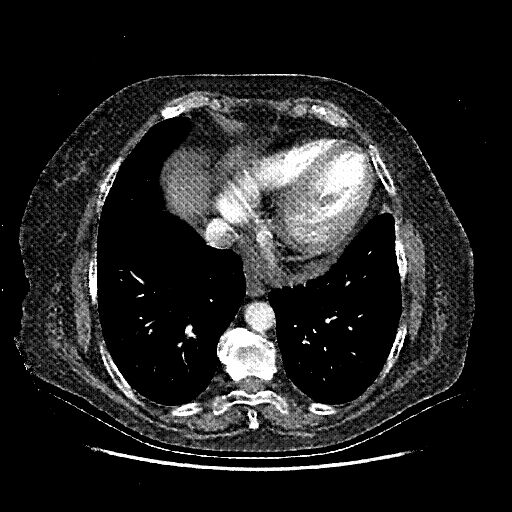

Generated VENOUS CT scan (A→B translation)

No window - Raw intensity values

Lung window (WL -600, WW 1500 β†’ Low βˆ’1350, High +150)

Mediastinum window (WL 40, WW 400 β†’ Low βˆ’160, High +240)